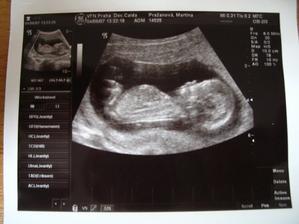

Dne 3.4.2007 to vypadá dle testů, že to vyšlo a my se snad dočkáme našeho vytouženého miminka a já nikdy nezapomenu děkovat a vážit si práce všeho personálu CAR u Apolináře. Dne 19.4.2007 nám bylo v CAR ultrazvukem potvrzeno, že opravdu čekáme naše vytoužené miminko. Dne 4.6.2007 jsme byli na genetickém UTZ ve 12+4.tt a UTZ dopadl na 1*. Dnes 26.7.2007 jsme byli na 3. ultrazvuku, jsme ve 20+2.tt a miminko je v naprostém pořádku. S maminkou už je to horši, ale snad všechno nakonec dobře dopadne. Dne 30.8.2007 jsme byli neplánovaně na 4. ultrazvuku a monitoru, protože maminka upadla na schodech, naštěstí je miminko v pořádku a neutrpělo žádnou újmu. Dnes 9.9.2007 jsme byli s tatínkem na 4D ultrazvuku v Gennetu Praha, máme krásné fotečky a DVD. Dozvěděli jsme se, že miminko v mém bříšku je holčička. Večer 9.9.2007 jsme naší holčičce vybrali jméno, je to Verunka.